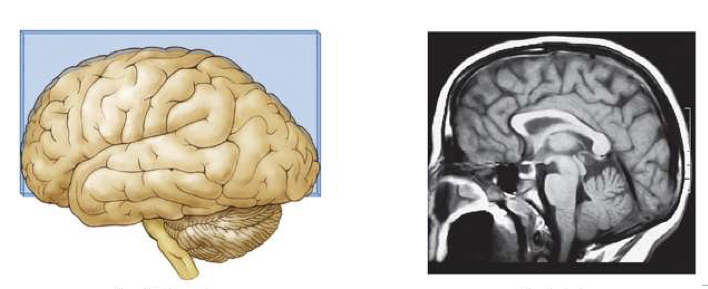

What is this brain plane called?

Sagittal Section

A cut from front to back in the middle, showing the brain from the side

like a profile view